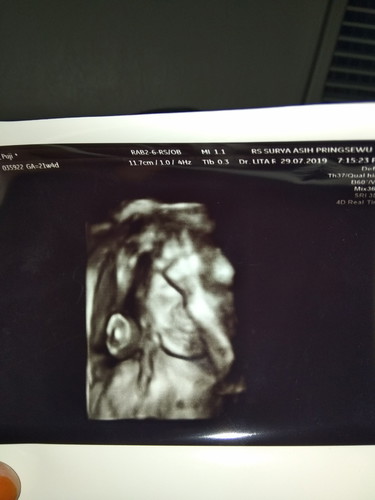

Alhamdulillah sy baru aja usg dan debay nya normal, sehat, tp perkiraan dokter lbh cepet katanya HPL 21 november klu kata bidan 7 desember.. Kata dokter Debay nya lg pusing mikirin kondangan tanganya di tarok jidat ??minta doanya ya bun moga di ksh kesehatan smpai lahir nnt amin